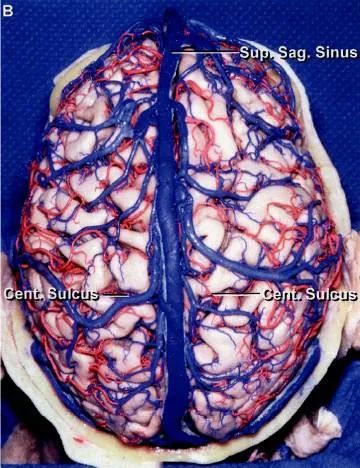

上矢状窦位于大脑镰凸缘附着处,前从鸡冠开始,沿颅内面的矢状沟向后行,至近枕内隆凸处,多偏向右移行为右横窦,也有的后端分叉,分别移行于左、右横窦(详后窦汇)。

上矢状窦的横切面呈三角形,由前向后逐渐增大。左右侧壁有大脑上静脉的开口,还有突入的蛛网膜颗粒。每侧还有三个静脉陷窝,是窦壁较薄的扩大部分。顶静脉陷窝最大,枕静脉陷窝次之,在前的额静脉陷窝最小。有作者记录:儿童静脉陷窝不明显,成年人的静脉陷窝发育良好;到老年,这些静脉陷窝有彼此连续的倾向,每侧几乎成一个长形的陷窝。静脉陷窝接受大脑上静脉的开口,每个静脉陷窝可接受1~3个静脉。静脉陷窝内有许多纤维横过,还有许多柱状、中隔状或弓形的蛛网膜颗粒从下突入至陷窝内。窦的下角也有许多横行纤维束横过。